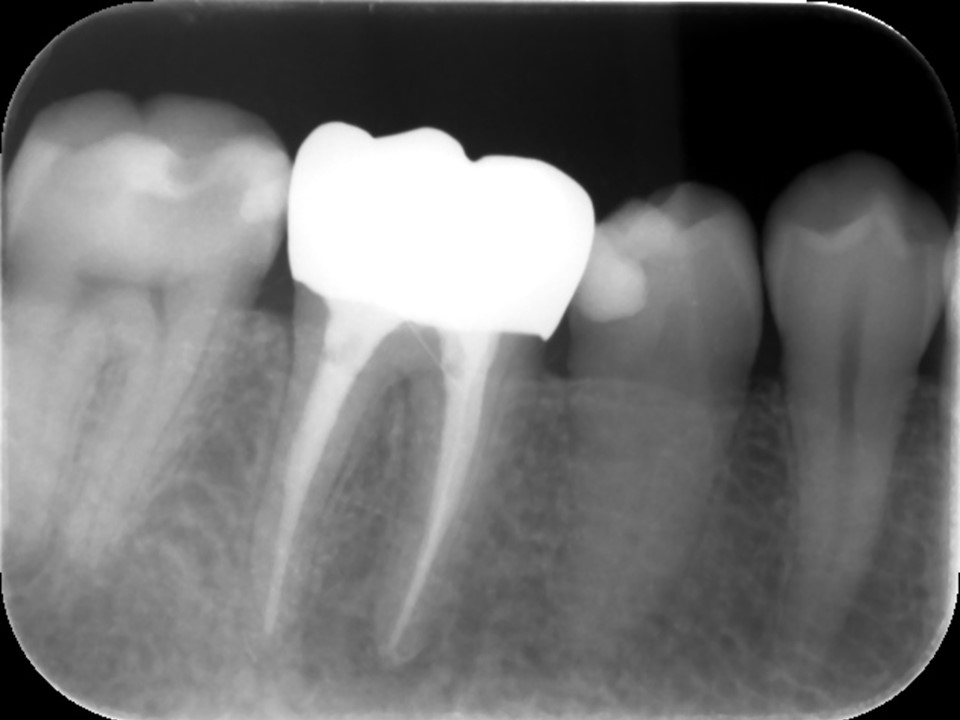

根管充填後レントゲンおよびCT画像です。

症状が消失したため、ガッタパーチャとバイオセラミックシーラーにて根管充填を行いました。炎症が強かったため、歯槽骨の吸収の範囲が術前よりも広がっています(矢印)。